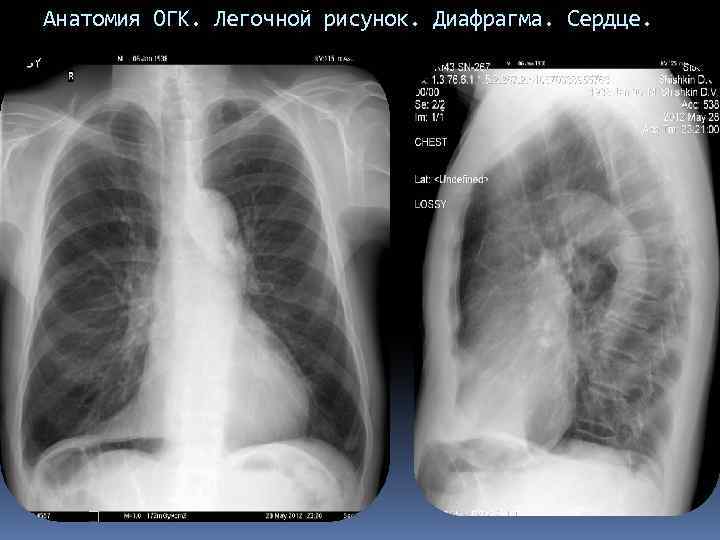

Анатомия ОГК. Легочной рисунок. Диафрагма. Сердце.